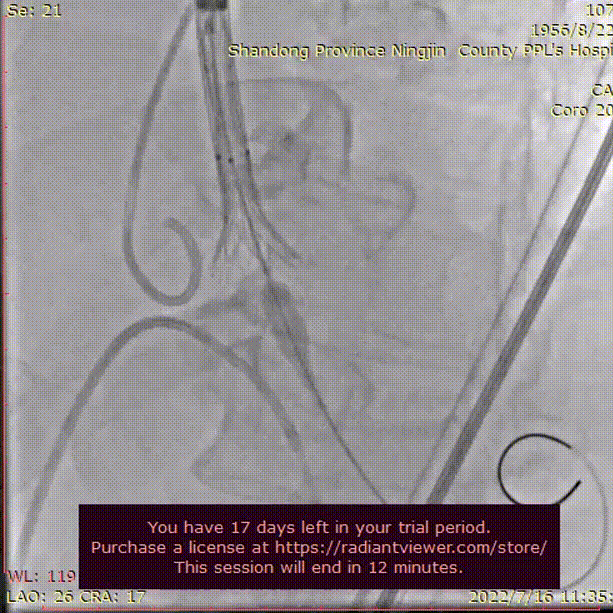

主动脉根部根部造影

造影评估

术者结合DSA影像,多角度观察瓣膜情况,在瓣膜释放至工作位造影。

初始定位释放

工作位

无明显返流,瓣膜形态佳,工作稳定。

工作位评估

完全释放